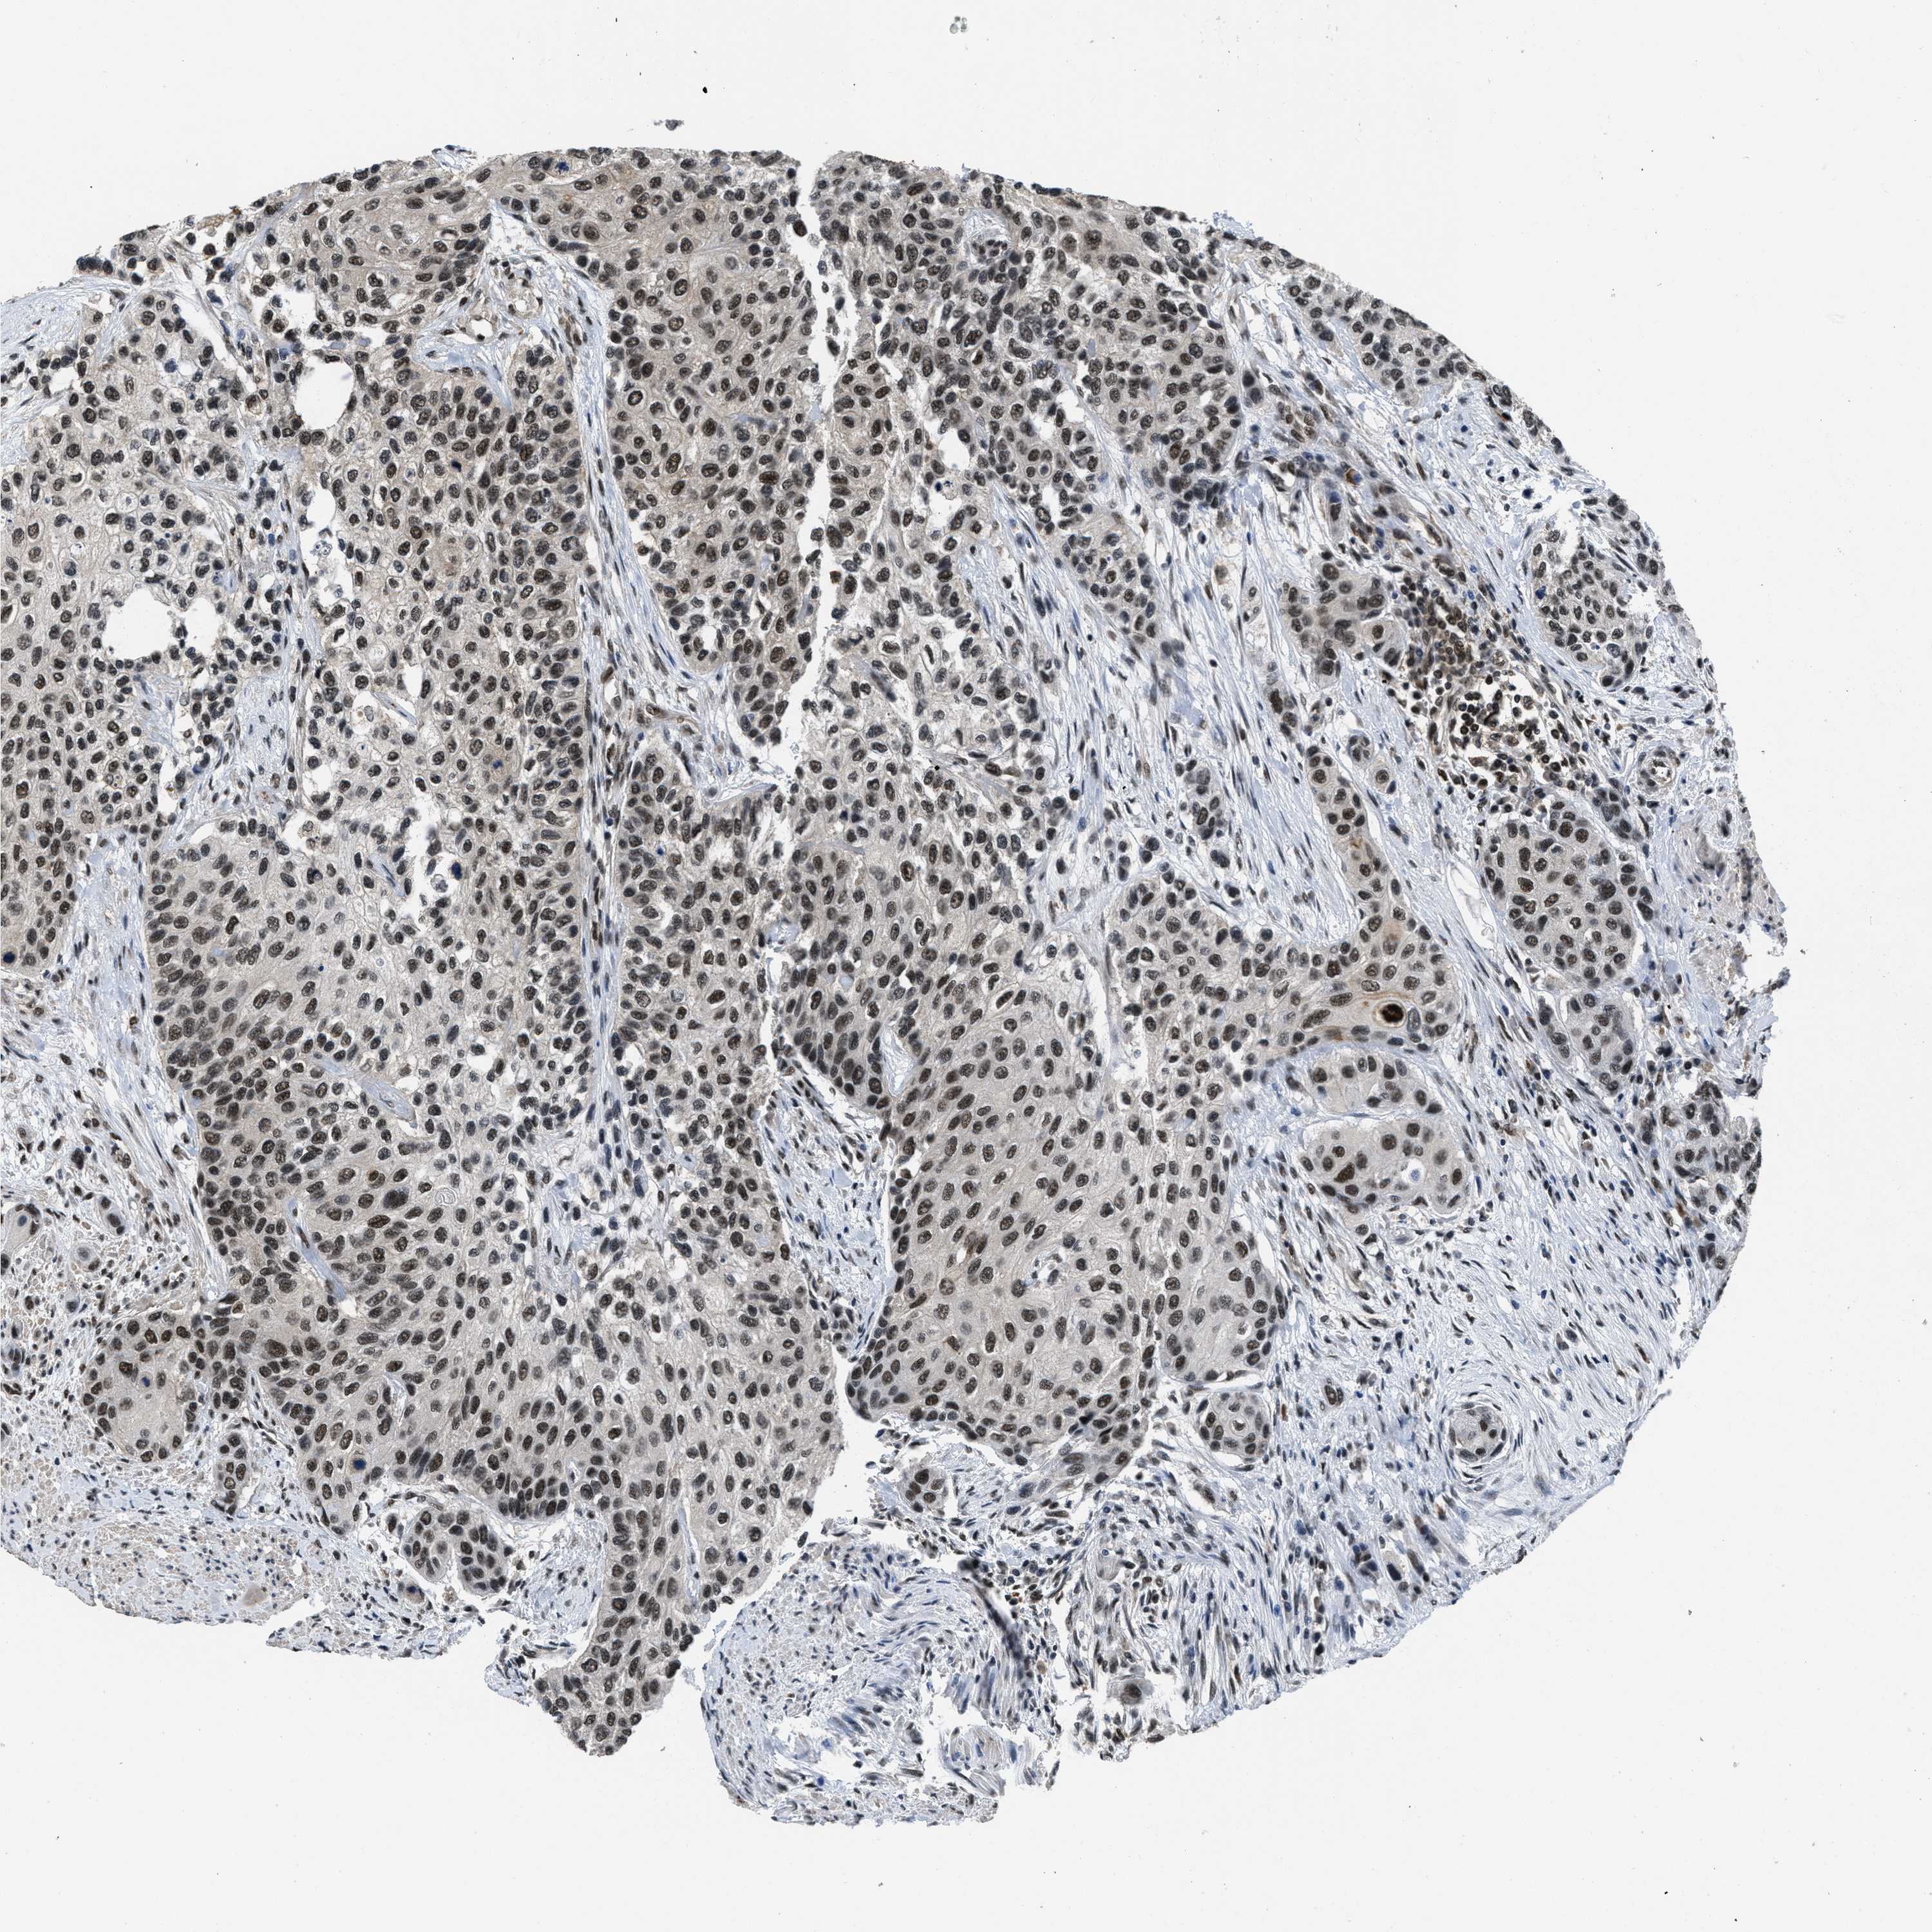

UROTHELIAL CANCER - Protein expressioni

A mouse-over function shows sample information and annotation data. Click on an image to view it in a full screen mode. Samples can be filtered based on level of antibody staining by selecting one or several of the following categories: high, medium, low and not detected. The assay and annotation is described here.

Antibody stainingi

Antibody staining in the annotated cell types in the current human tissue is reported as not detected, low, medium, or high, based on conventional immunohistochemistry profiling in selected tissues. This score is based on the combination of the staining intensity and fraction of stained cells.

Each image is clickable and will lead to virtual microscopy that enables deeper exploration of all samples and also displays staining intensity scores, fraction scores and subcellular localization as well as patient and tissue information for each sample.

Antibody HPA011880

Antibody CAB017786

Urothelial carcinoma, Low grade

Urothelial carcinoma, High grade